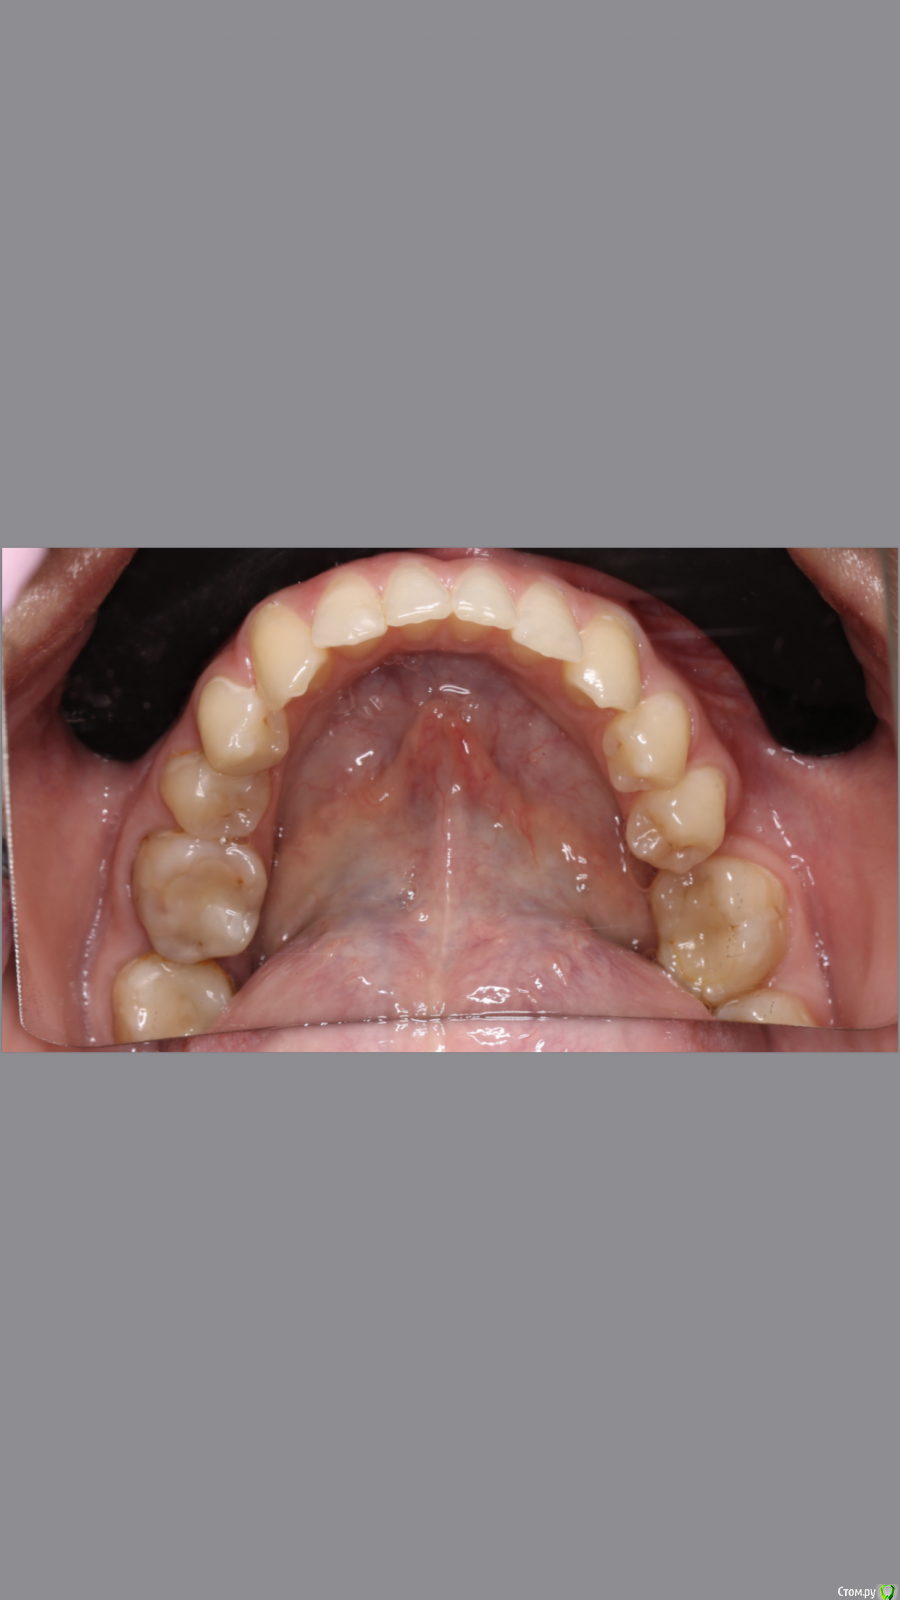

dr.Dre Опубликовано 8 июня, 2019 Поделиться Опубликовано 8 июня, 2019 Добрый вечер.Коллеги помогите грамотно скласть план лечения?С чего начинать ,терапия,ортодонтия ортопедия Ссылка на комментарий

Monkey Опубликовано 19 июня, 2019 Поделиться Опубликовано 19 июня, 2019 Добрый вечер.Коллеги помогите грамотно скласть план лечения?С чего начинать ,терапия,ортодонтия ортопедияСанация, удаление 8-х, ортодонтическое лечение с раскрытием места 36,23 (заодно и среднюю линию откорректируете), протезирование Ссылка на комментарий